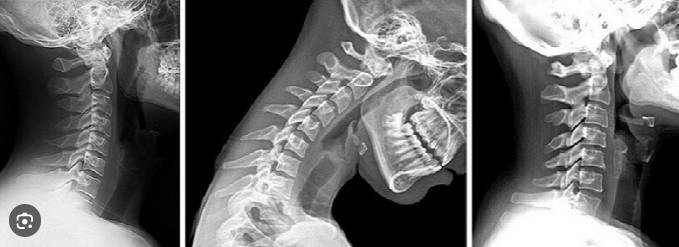

Beyin ve sinir cerrahisi uzmanından özellikle genç ve orta yaşlılara kritik cep telefonu uyarısı yapıldı. Cep telefonlarının bağımlılık seviyesinde kullanımının sağlık üzerindeki ciddi etkilerini açıklayan uzman duruş bozukluğunun etkilerine dikkat çekti.

Sağlık Bakanlığı Dr. Abdurrahman Yurtaslan Ankara Onkoloji Eğitim ve Araştırma Hastanesi Beyin ve Sinir Cerrahisi Uzmanı Prof. Dr. Aşkın Esen Hastürk, akıllı cep telefonlarının aşırı kullanımının sağlık üzerindeki olumsuz etkilerine dikkat çekti.

Prof. Dr. Hastürk, cep telefonu kullanımının gençler ve orta yaş grubunda bağımlılık seviyesine ulaştığını söyledi. Akıllı telefonların sağladığı kolaylıkların yanında ciddi sağlık sorunlarına da neden olduğunu vurgulayan Hastürk, "Bu cihazların kas iskelet sistemi, eklemler ve sinir dokusu üzerinde yarattığı tahribat en çok bilinen ve tespit edilen sorunlardır" dedi

Aynı duruş pozisyonunda sürekli tekrarlayan el, bilek ve dirsek hareketlerinin eklem bölgelerinde sertleşme, kireçlenme ve iltihaplanmaya neden olarak sinir dokusunda baskı ve hasar oluşturduğunu belirtti. Hastaların en sık şikayet ettiği problemler arasında ağrı ve uyuşmanın yer aldığını kaydetti.